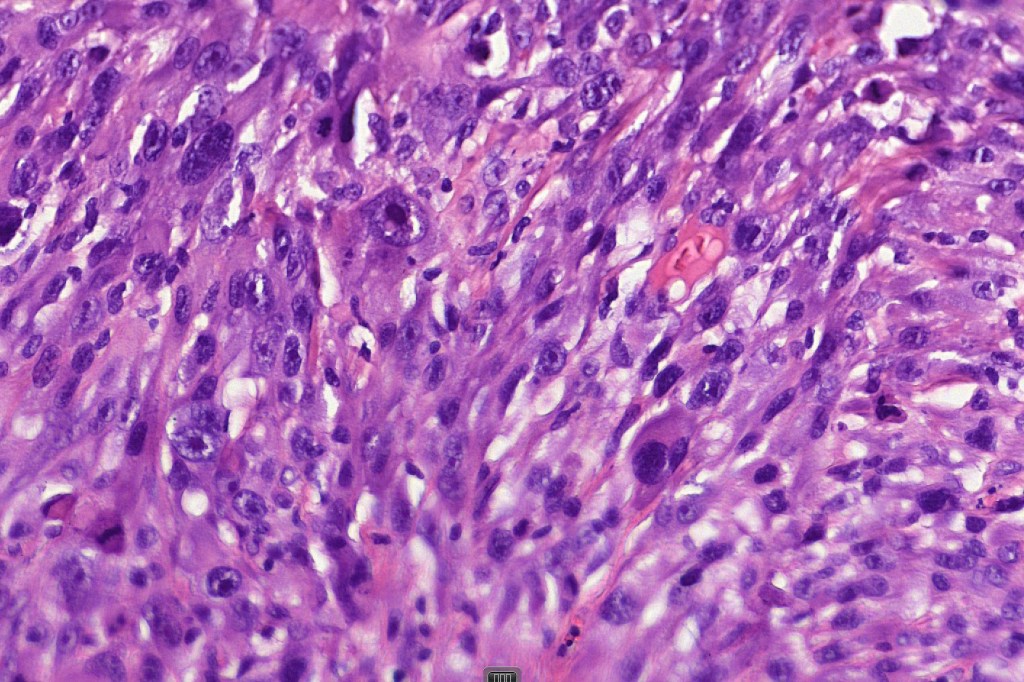

These are very rare variants of amelanotic or virtually amelanotic melanoma where a primary melanoma or a metastasis shows partial (DN) or complete loss (UN) of recognizable histological and immunohistochemical features. The histology may lead the pathologists to consider lymphoma, sarcoma, anaplastic carcinoma or a small cell tumor. Some examples of rhabdoid melanoma & melanoma with heterologous differentiation probably belong in this category. Ultimately, if there is no identifiable/recognizable primary tumor, diagnosis may only be comfortably made with next-generation sequencing. In the cases presented below, immunohistochemistry was of value in determining the melanoctic nature of the tumor (undifferentiated melanoma).